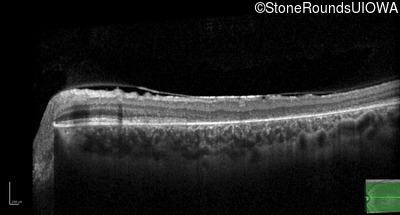

| AR Stargardt Disease | ABCA4 | Asp507Tyr GAT>TAT | IVS40+5 G>A | AR |